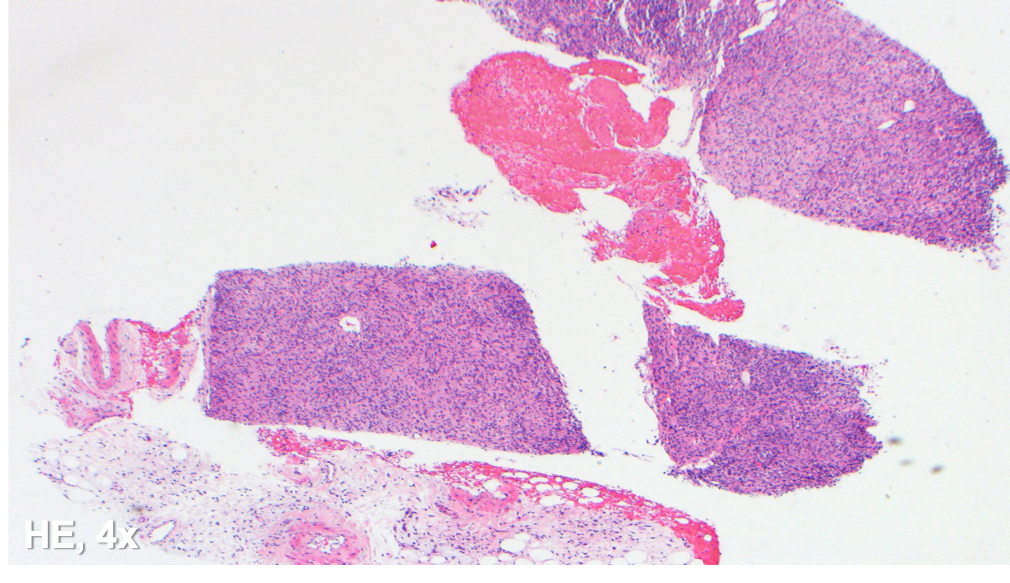

The specimen shows a tissue core with a diffuse histiocytic proliferation and scattered plasma cells. No lymph node architecture is identified. Many of the cells are plump and with abundant foamy cytoplasm, while others appear spindled in morphology.